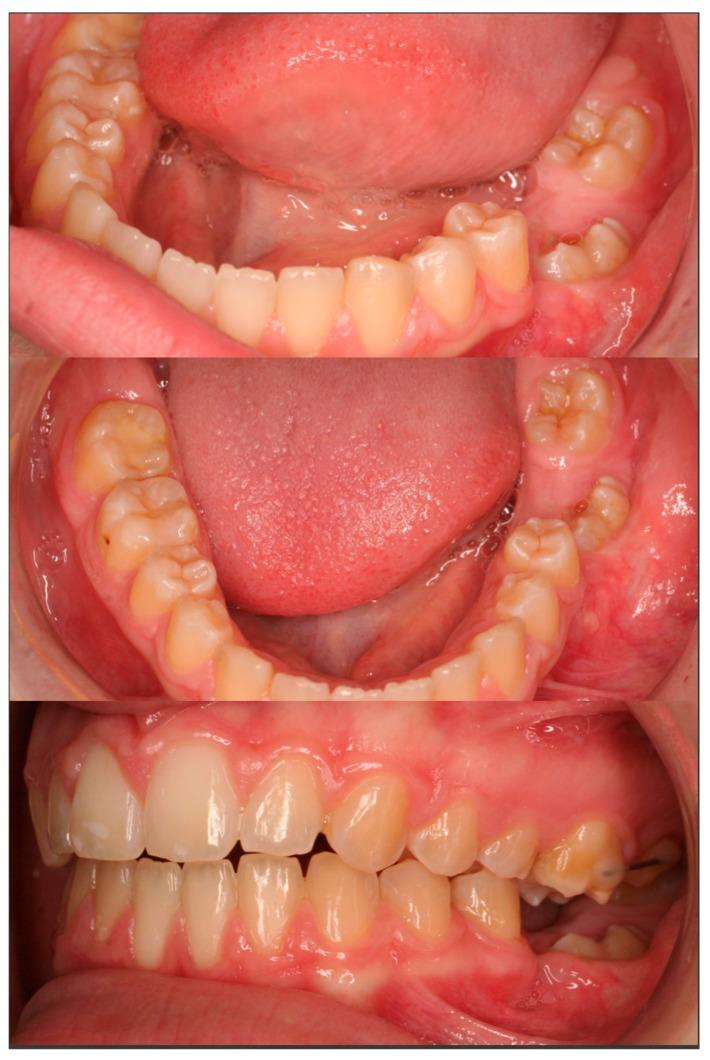

The purpose of this paper is to present a case of an impacted mandibular first molar associated with a dentigerous cyst and a missing mandibular second molar in an 11-year-old girl that was treated with combined surgical and orthodontic procedures. After clinical and radiographic evaluation, marsupialization of the cyst was decided, and a molar attachment was bonded on the buccal side of the impacted molar as a part of a full orthodontic treatment with fixed appliances. After 18 months of orthodontic traction, the molar was moved to a more advantageous position, and new bone apposition was observed on the site of the cystic lesion. Histological examination confirmed a dentigerous cyst. The molar was left to erupt spontaneously for 14 more months. A functional occlusion was finally achieved. An interdisciplinary approach proved to be an effective modality in treating a large dentigerous cyst associated with a deeply impacted first mandibular molar, presenting many advantages, such as new bone apposition and patient comfort.

本文旨在介绍一例11岁女孩的病例,该患者下颌第一磨牙阻生并伴有含牙囊肿,同时下颌第二磨牙缺失,采用手术和正畸联合治疗。经过临床和影像学评估后,决定对囊肿进行袋形术,并在阻生磨牙的颊侧粘结磨牙附件,作为固定矫治器全口正畸治疗的一部分。经过18个月的正畸牵引,磨牙移动到更有利的位置,并且在囊性病变部位观察到新骨形成。组织学检查证实为含牙囊肿。磨牙又自行萌出了14个月。最终实现了功能性咬合。跨学科方法被证明是治疗与下颌第一磨牙深度阻生相关的大型含牙囊肿的有效方式,具有许多优点,如新骨形成和患者舒适度高。